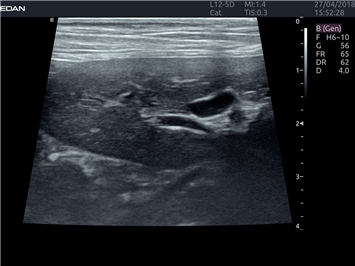

EDAN Acclarix LX4 VET представляет собой профессиональную ультразвуковую систему, специально разработанную для ветеринарных исследований. Сочетание стабильности, высокой производительности и эффективности делает эту систему идеальным выбором для современной ветеринарной практики.

Передовые технологии визуализации:

Инновационные технологии обработки изображений:

• Адаптивная визуализация тканей:

• Оптимизация изображения для различных видов животных

• Улучшенная детализация структур

• Мультилучевое сложно-составное сканирование (SCI):

• Повышенная четкость изображения

• Улучшенная визуализация сложных анатомических структур

• Технология подавления зернистости:

• Снижение шумов изображения

• Повышение диагностической ценности